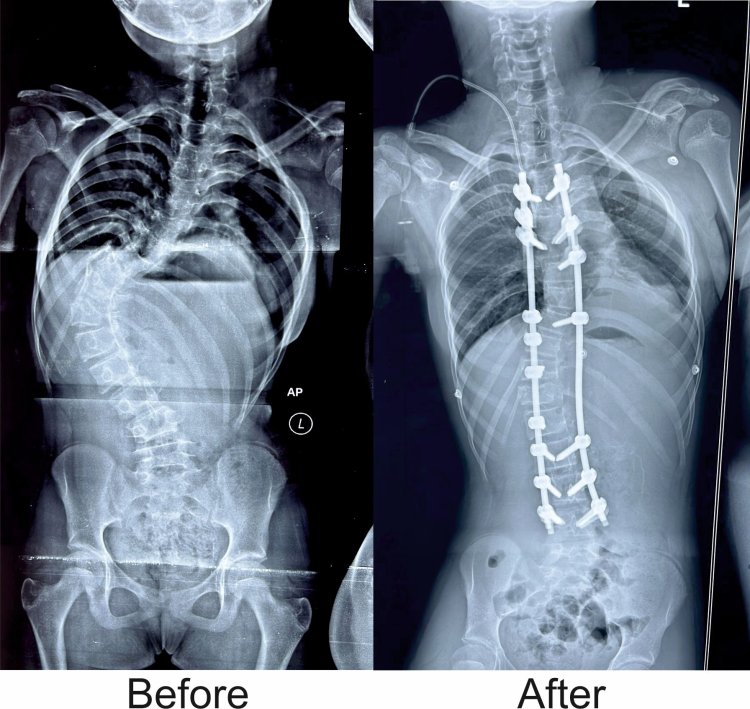

Bhubaneswar: Kalinga Institute of Medical Sciences (KIMS), Bhubaneswar has successfully given a new lease of life to a teenage girl from Bhadrak, who was battling a spinal deformity known as Scoliosis. The abnormal curve in her spine gave it an ‘S-shaped’ appearance, threatening her promising future. However, thanks to the expertise of the doctors at KIMS, her spine was meticulously corrected in a recent complex operation, and she is now on the path to a full recovery, ready to embrace a normal life once again.

Dr. Rout explained that the spinal deformity the girl suffered from is known as "idiopathic scoliosis," a condition that typically develops between the ages of 10 and 15 and if left untreated, can lead to severe deformities and significantly impact self-confidence and self-esteem. Such patients often become targets of ridicule due to their appearance. Correcting the deformity at an early age is crucial, as it becomes more challenging to treat an advanced age.

Notably, Dr. Rout, who is also the Secretary of the Spine Society of Odisha, accomplished the challenging operation in an impressive four hours, a procedure that typically takes 7-8 hours. The success of the surgery was further aided by the use of an advanced 'intraoperative neuro monitoring’ machine, which promptly alerts the doctors to any potential complications during the procedure.